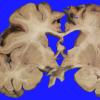

VASCULAR

Cavernous Angioma (10)